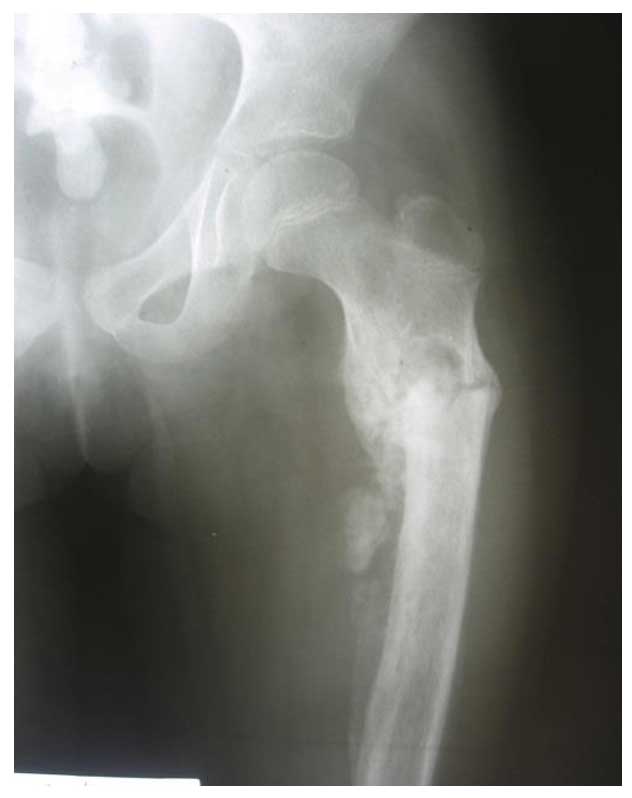

Ameliyat Öncesi: Röntgende proksimal femurda kırığa bağlı deformite, düzensizlik ve periost reaksiyonu görülmekte.